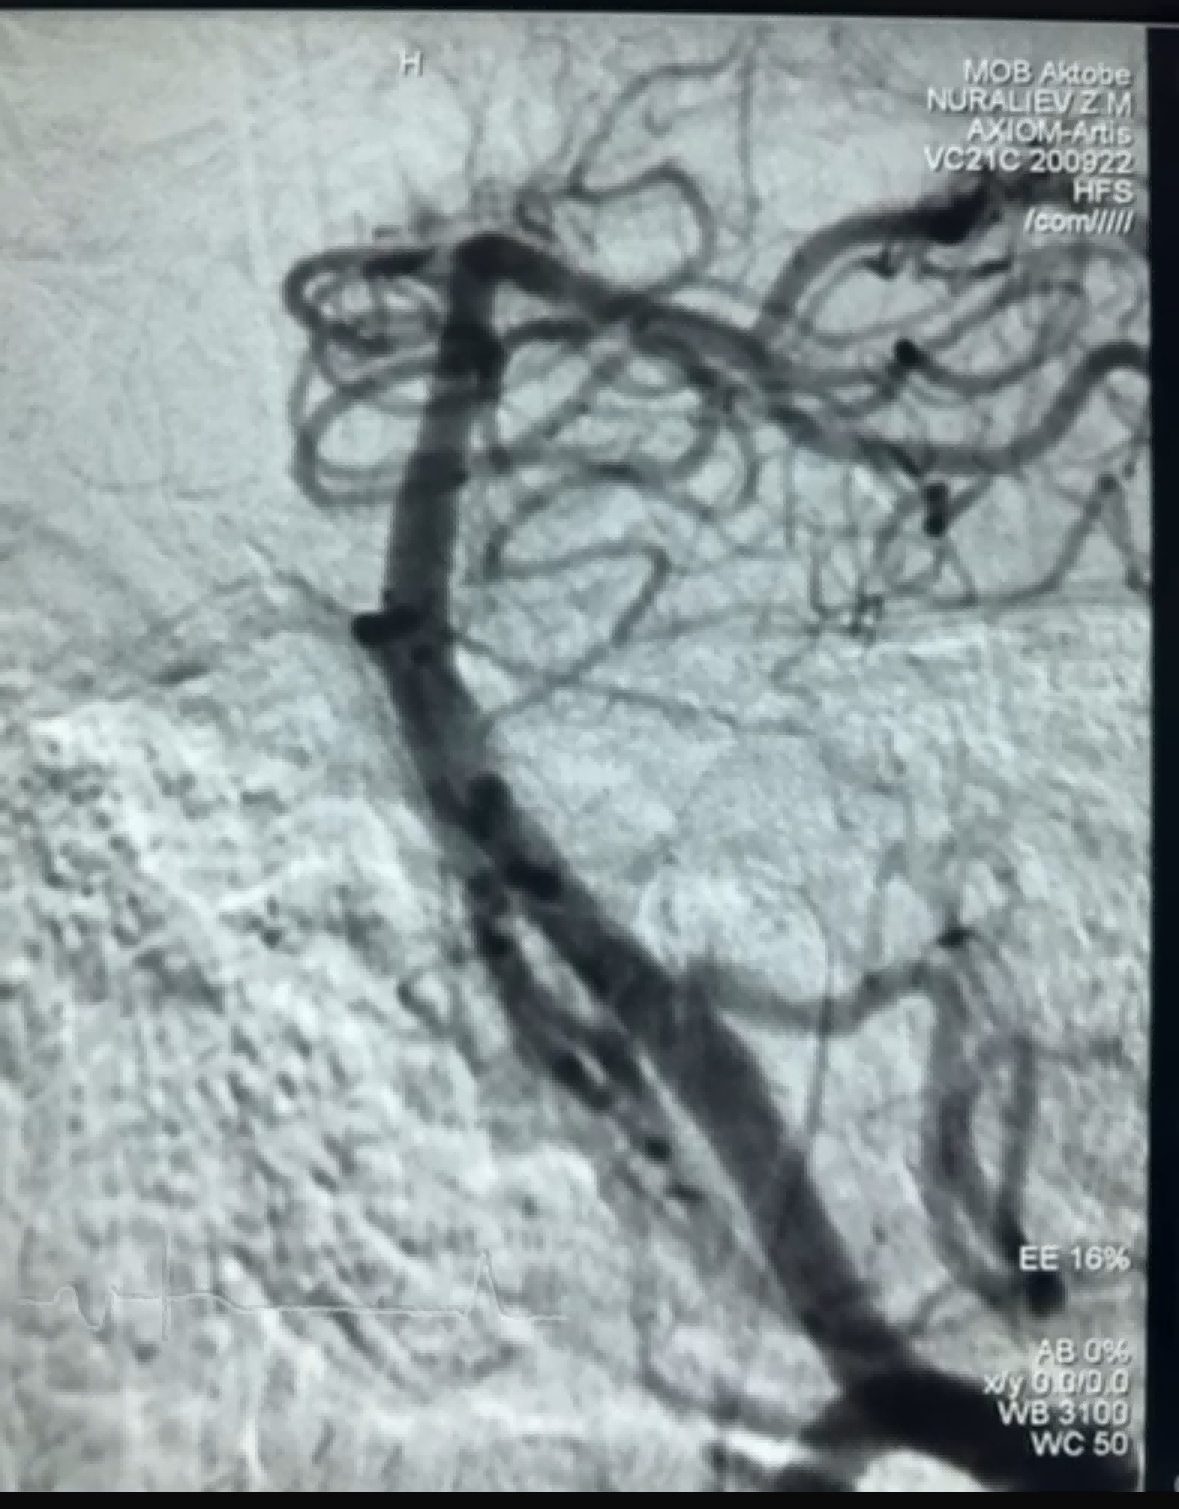

Yakın zamanda NeuroSafe Medical Co., Ltd. firmasının Dredger Stent Retriever cihazı kullanılarak başarılı bir trombektomi vakası gerçekleştirildi. Dredger Stent Retriever, intimal hasar riskini büyük ölçüde azaltan invaziv olmayan yumuşak bir uca sahiptir ve esas olarak boşluk değişikliklerini sıkıştırarak kan pıhtılarını yakalayan benzersiz, özel şekilli bir delik tasarımına sahiptir.